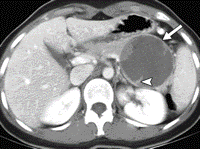

- Kontrastlı KT və ya MRT standart müayinədir, şişi və yayılma dərəcəsini müəyyənləşdirilməsində önəmlidir.

- Görüntüləmdə: erkən arterial fazada contrast tutan və venoz fazada yuyulan, MRT-də hipointens, ətraf toxumalara invaziv, böyüməyə meylli, baş nahiyyəsində yerləşərək xoledoxu və pankreatik axacağı genişləndirən (“iki axacaq simptomu”) törəmə